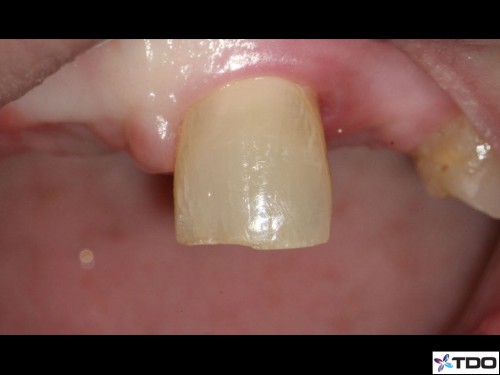

47 yof. Symptomatic partially necrotic pulp. First visit instrumented with #15K to length. Second visit apically gauged to a size 40.